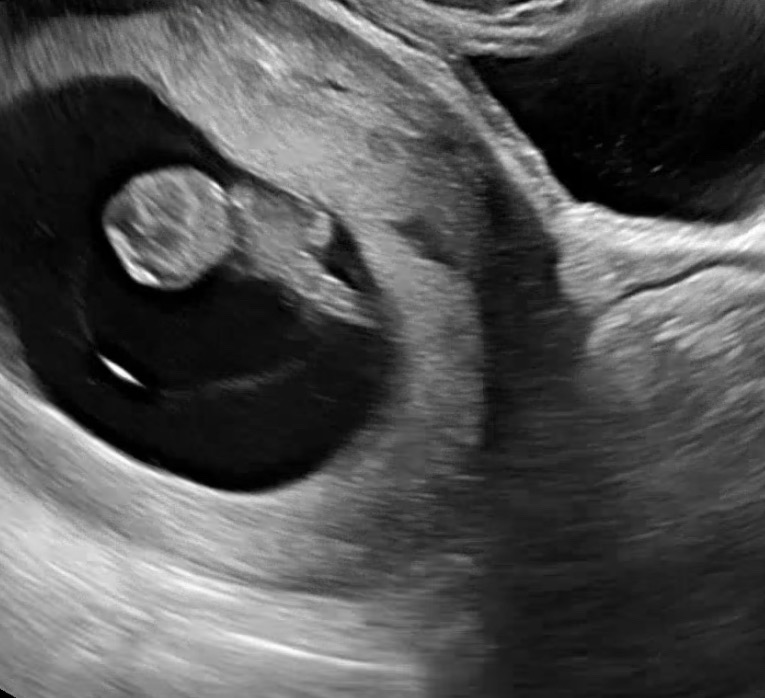

지옥같은 입덧.. 그리오 오늘 젤리곰을 본 날 🧸

저는 6주부터 시작된 입덧(체덧 토덧)이 너무 심해서 하루종일 구토만 하고, 나중에는 피까지 토했어요. 먹을 수 있는 게 누룽밥(숭늉)과 포카리 음료 밖에 없었어서, 2주 사이에 체중이 5키로 넘게 빠졌고… 제가 영양 섭취를 못해서 혹여나 아기한테 안좋은 건 아닌지 노심초사하며 지내다가 오늘이 정기검진 날이라 병원에 갔어요. 다행히 제 입덧이나 체중감소와 별개로 아기는 폭풍 성장..!!! 2주전에 0.8cm였는데 오늘은 2.3cm나 되네요! 심장소리도 190bpm이 넘는다면서 애기는 엄청 건강하다구 안심시켜주셨네요..ㅠㅠ 그동안 입덧때문에 정말 죽을만큼 힘들었는데, 꼬물꼬물 움직이는 젤리곰을 보고나니 조금은 나아지는 기분이에요! 병원 다녀와서 아기를 위해 힘내자는 마음으로 닭죽 한그릇을 다 먹어봤어요! 모든 예비 엄마들 화이팅 입니다ㅠㅠ😭🩷